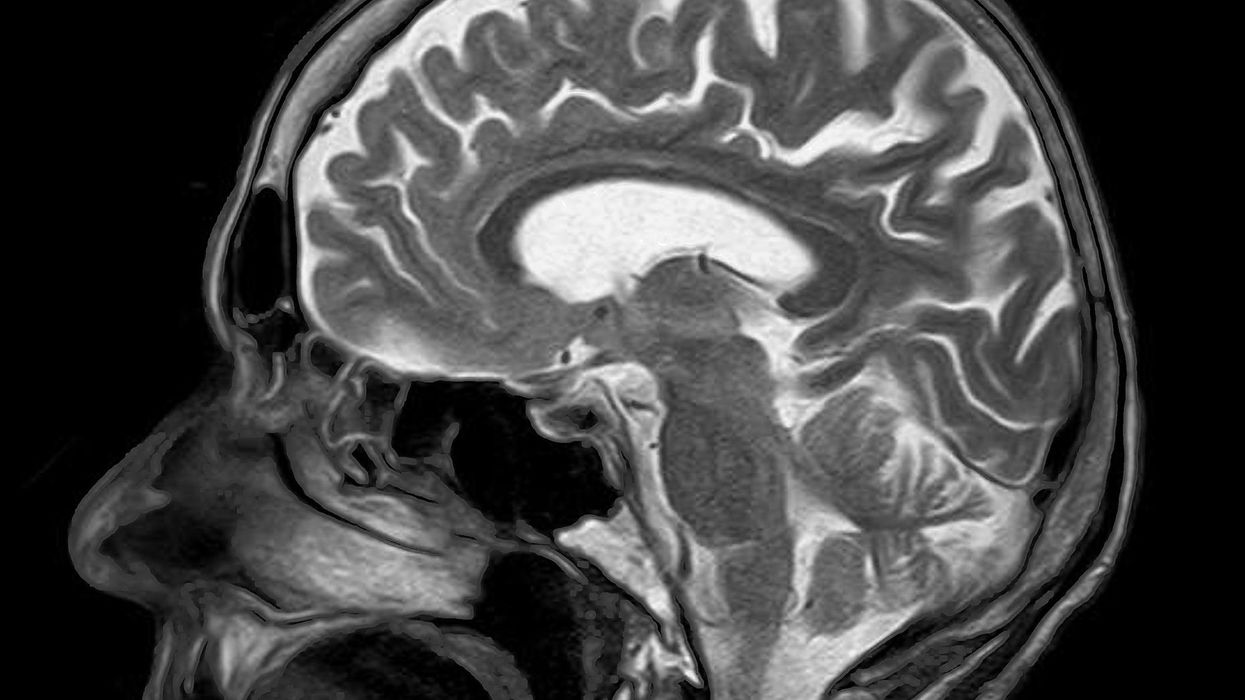

Pixabay/Creative Commons